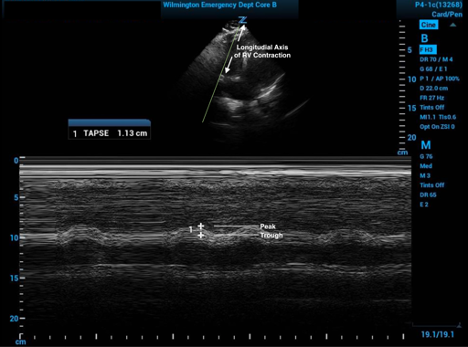

The measured difference of the distance between the peak and trough of this tracing will produce the TAPSE value. Care must be used to place the measurement points on the same side of the tricuspid valve (typically towards the top of the screen) so as to not include the thickness of the valve itself (see Figure 2). This value corresponds to the change in right ventricular height during a cardiac cycle.3

Figure 2. M Mode with tracer spike in the RV posterior tricuspid valve leaflet annulus showing the change in RV height throughout the cardiac cycles with both measurement points on the same side of the valve

One limitation of using TAPSE is a lack of a consensus for cutoff values to be used. The patient in Figure 2 has an abnormal TAPSE by just about any published cutoff, but there are some that will fall into a gray zone. The range in retrospective studies that have correlated with RV dysfunction as well as increased mortality attributable to acute PE are generally 15mm-20mm.6-11 A joint abnormal cutoff established by the American Society of Echocardiography and the European Association of Cardiovascular Imaging is ≤ 16mm.12 One must take care when placing the M-mode tracer spike, as small misplacement and poor placement of the angle of the M-mode cursor can translate to large differences in measurement.